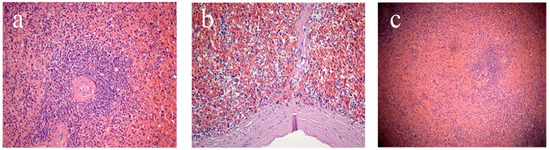

The second stage involved assessment of microscopic characteristics, which included analysis of the state of the capsule (thickened/not thickened, the presence of hyalinosis) and trabeculae (thickened/not thickened, the presence of hyalinosis); determination of the white pulp (WP)/red pulp (RP) ratio; as well as characterization of WP follicles (size, presence or absence of generative centers, severity of the marginal zone), and the state of the central arteries of follicles (the walls are thickened/not thickened, the presence of hyalinosis) (Figure 1). The study of the RP assessed the state of the reticular stroma (sanguineous/non-sanguineous, the presence of erythrocytes, macrophages, plasmocytes) and sinusoids (sanguineous/non-sanguineous).

Figure 1. Splenic sections: (a) white pulp follicle, (b) subcapsular zone, (c) marginal zone. Staining with hematoxylin and eosin. Magnification ×200 (a,b), ×100 (c).